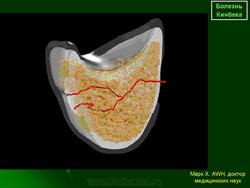

При рентгенологическом исследовании в ранней стадии заболевания отмечается смазанная картина структурного рисунка полулунной кости. Со временем тень ее становится более интенсивной по сравнению с соседними костями запястья, размеры уменьшаются, появляется неровность контуров, могут возникать кистозные изменения. В дальнейшем развивается фрагментация, сплющивание и прогрессирующая деформация полулунной кости, которая часто приобретает треугольную форму. Смежные суставные щели при этом расширяются. В редких случаях происходит уменьшение размеров полулунной кости с явлениями повышенного склероза костной ткани, напоминающего мраморную болезнь. В позднем периоде заболевания рентгенологически определяются явления остеоартроза.

Фигура 2: